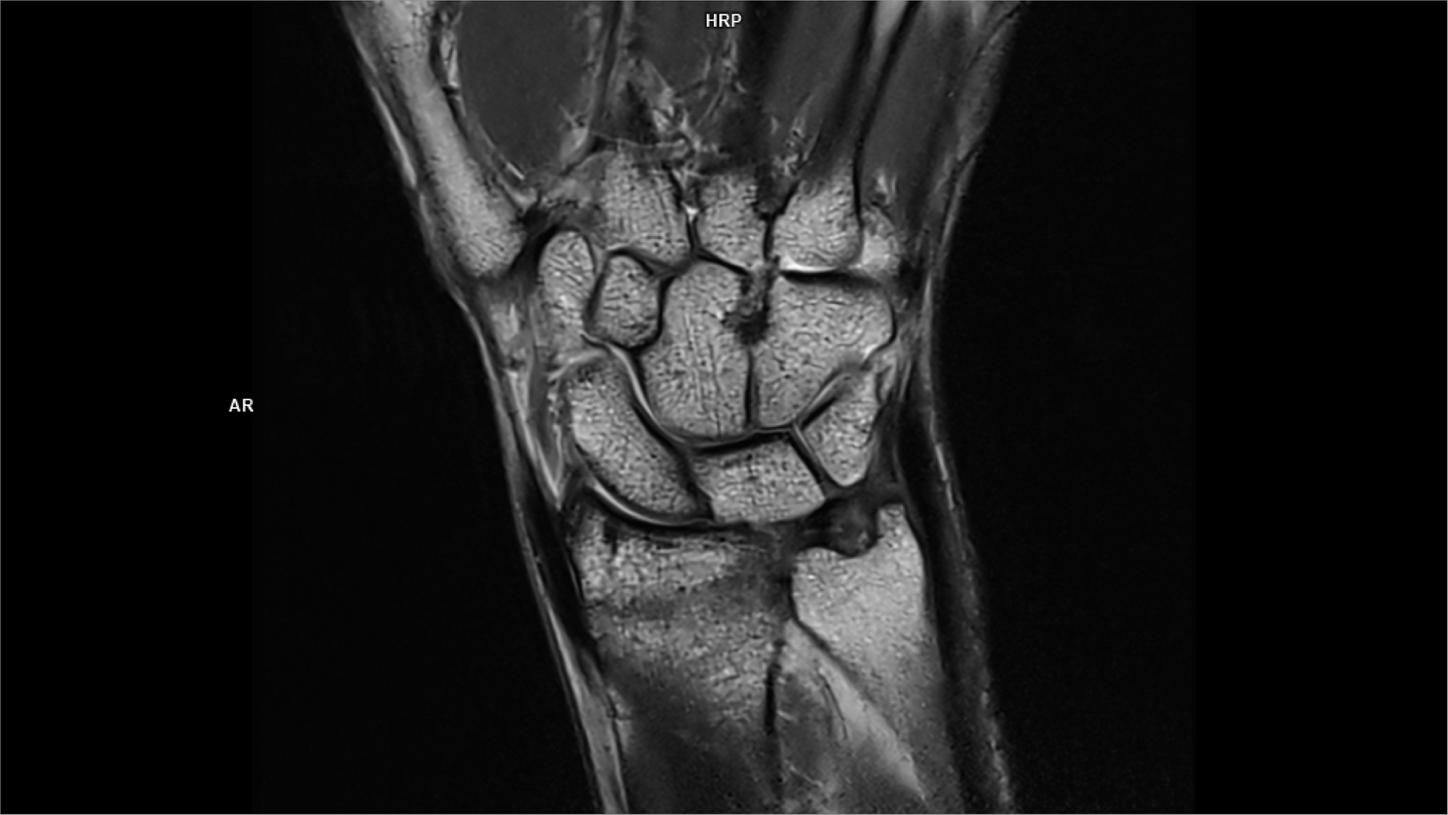

Coronal MRI Scan Diagram Quizlet Coronal Pd Mri The mri allows accurate assessment of any pathologic changes of the structures of the shoulder, including the glenoid labrum, the humeral head, the articular. Protocol specifics will vary depending on mri hardware and software, radiologist and referrer preference, patient. Many standard shoulder protocols will include the following fast spin echo sequences: The role of mri in. In this article we. Coronal Pd Mri.